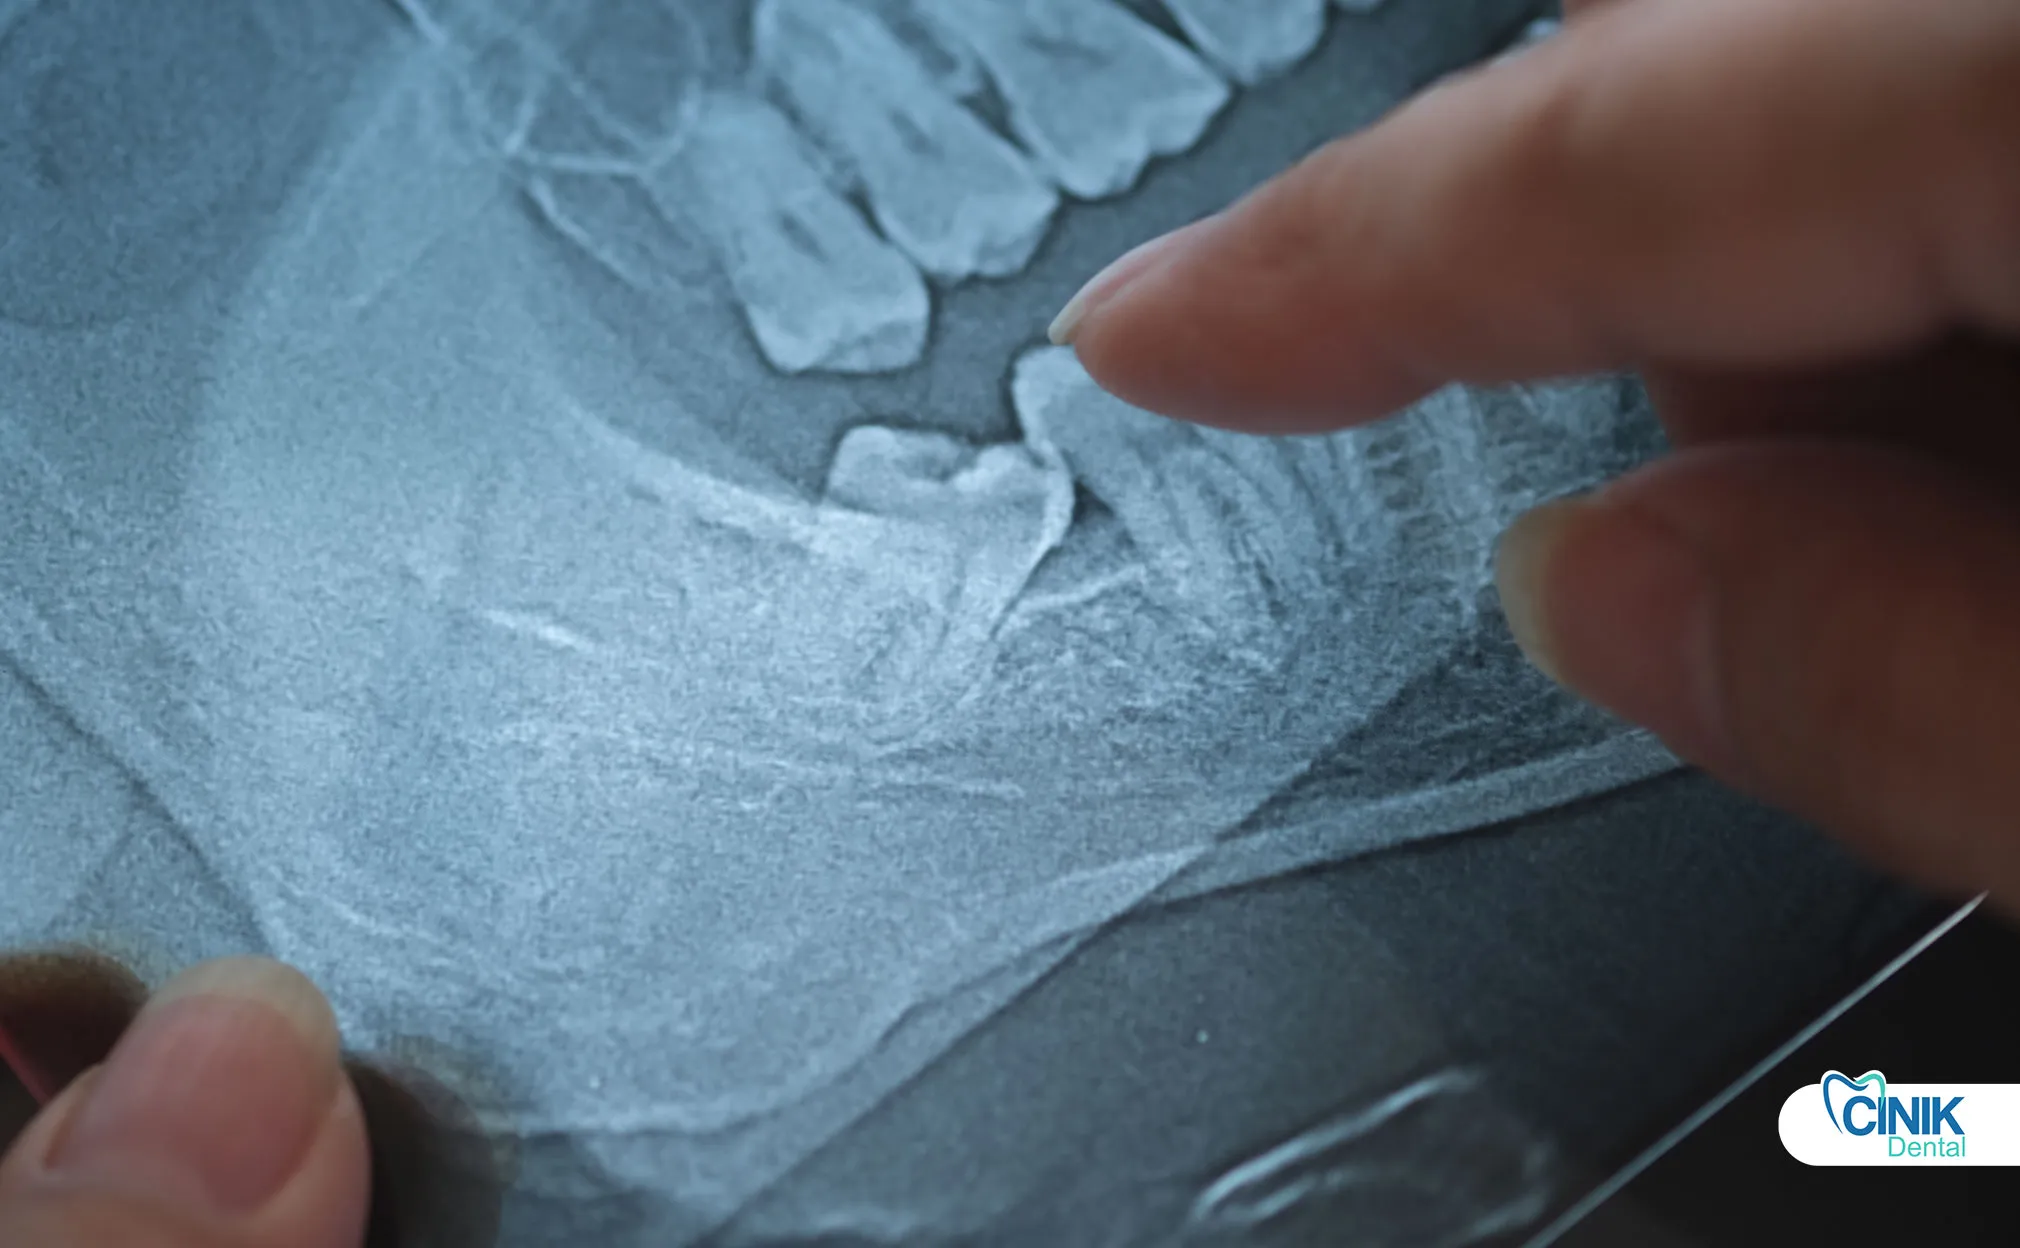

Radiographic imaging provides essential anatomical information:

Panoramic radiography (OPG) serves as the standard initial screening tool. This two-dimensional image reveals:

Tooth angulation and impaction depth

Root morphology and curvature

Relationship to adjacent teeth

Approximate nerve canal positioning

Research by Guerrero et al. (2020) demonstrates that CBCT evaluation reduces nerve injury rates by 40% compared to panoramic-based planning in high-risk cases.